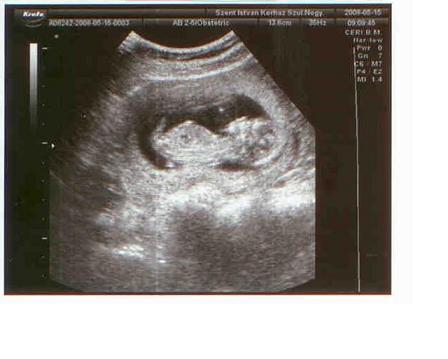

Most hétvégén lehet elmegyünk 4D-re. 16 hetes leszek már szombaton, és ilyenkor már tökjól látszik a baby, meg a nemét is nagyon-nagyon szeretném tudni, úh beszélgetek vele folyamatosan, hogy igérje meg, h széttárj a lábikóit, és akkor elmegyünk meglesni őt...de ha rossz lesz, és még úgy is forul, h nem láthatjuk rendesen, akkor örök harag egy időre, mert 150fontba kerül. (52e ft)

Kérdés. Én hivatalosan mensi szerint nov.1-re lettem volna kiírva, de a 12 hetes uh-n 3 nappal idősebbnek minősítették a babyt, így okt 29 lett belőle.Szerintetek melyiket vegyem "konkrétnak"? Az az igazság, hogy 3 nappal szerintem nem fogant hamarabb, esetleg 1 vagy 2-vel...úh most nemtom... Segítsetek!